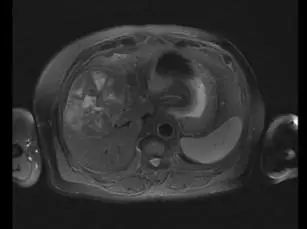

7、 患者转化成功后二次MDT

图8. 患者转化前MRI对比

图9. 患者转化后MRI对比

本例患者转化成功后目前处于无瘤状态,PIVKA-II逐步降至正常水平,是否可以“无药”是业界亟待回答的问题,我们暂时给予靶免的维持。